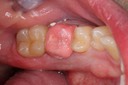

Kyle Chock #19 pre-op